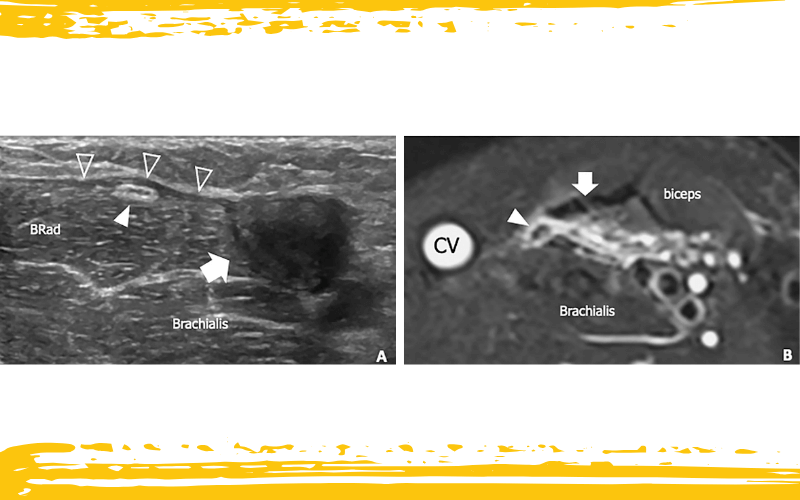

Neuropatía del nervio cutáneo lateral del antebrazo (LCNF) en un paciente con rotura distal del tendón del bíceps no reparada, a las 2 semanas del traumatismo.

A. La imagen ecográfica transversal muestra el LCNF (punta de flecha) situado en estrecha proximidad al muñón proximal retraído del tendón del bíceps (flecha). El nervio aparece alterado, con un epineurio anormalmente engrosado e hiperecogénico, consecuencia de los cambios traumáticos. Obsérvese el engrosamiento hipoecoico postraumático de la fascia braquial (puntas de flecha vacías) como manifestación de los cambios edematosos fasciales. BRad: braquiorradial.

B. La imagen axial en RM ponderada en T2 tSE con supresión grasa del mismo paciente, obtenida unos centímetros proximal al nivel de la imagen A, demuestra un LCNF ligeramente aumentado de tamaño (punta de flecha) discurriendo entre el tendón del bíceps (flecha) y la vena cefálica (CV). El nervio se encuentra inmerso en un área de edema de partes blandas que se extiende desde el nivel de la rotura tendinosa hasta la unión miotendinosa proximal.